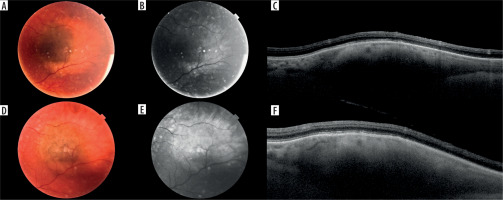

Figure 2

Small melanocytic lesion in a 68-year-old patient with no documented growth over a period of 4 years: A) color photography of the lesion at the first visit; B) autofluorescent photography of the lesion at the first visit; C) optical coherence tomography scan through the lesion at the first visit; D-F) corresponding images of the same lesion at the last follow-up